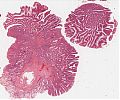

Abb. 654: Lupenvergrößerung eines kolorektalen villösen Adenoms (aus: Rosai Collection, Sem. 581).

Tubulovillöses Adenom

Abb. 655: Lupenvergrößerung eines tubulovillösen Adenoms (aus: Atlas der Organpathologie).